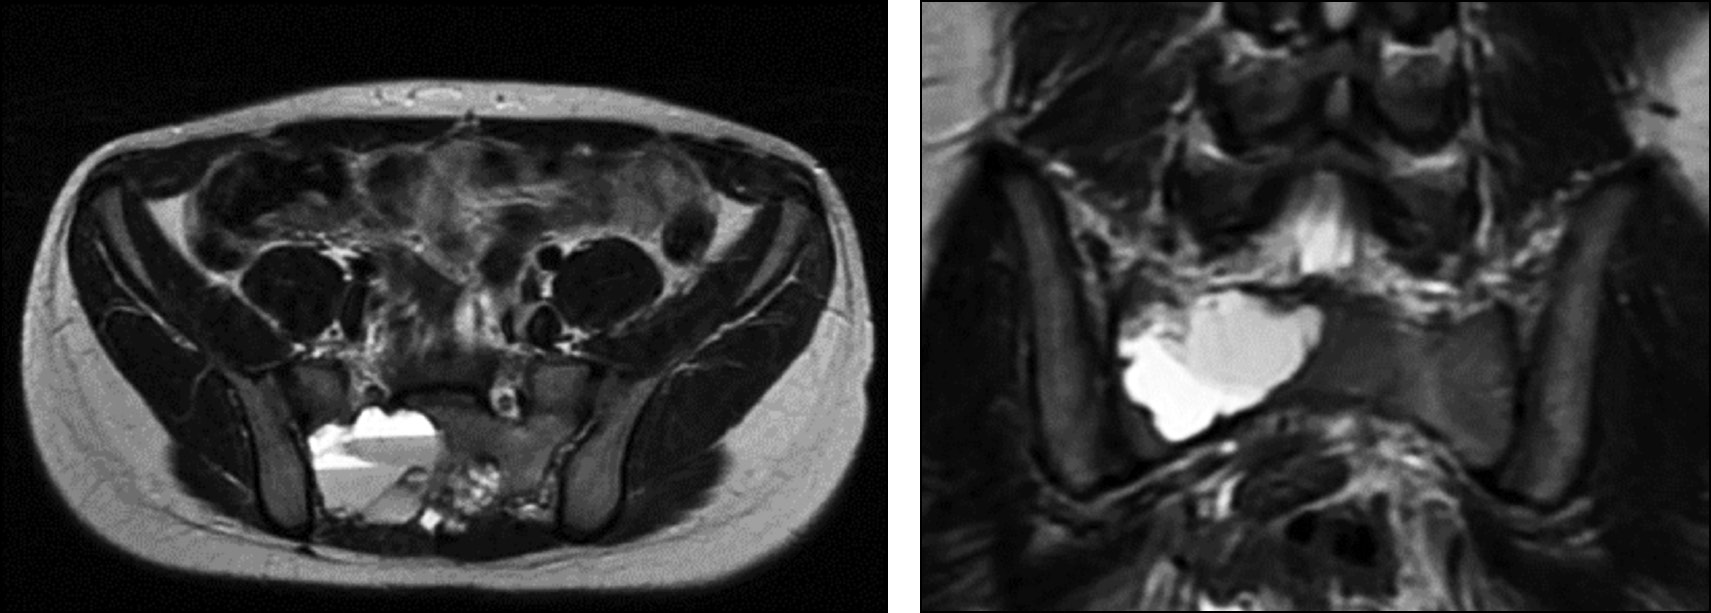

Рис. 2. МРТ на момент первой госпитализации. Киста представлена гигантской опухолью со множеством камер с разными уровнями жидкости. Определяется компрессия невральных структур, сдавление органов таза.

Fig. 2. An MRI scan at the time of the initial hospitalization revealed a cyst in the form of a large tumor with multiple chambers containing different levels of fluid. The MRI also showed compression of neural structures and pelvic organs.

Рис. 4. МРТ-картина до начала лечения. Киста представлена объёмным образованием, однако многокамерность опухоли выражена нечётко, что заставляет думать об ином процессе. Также отсутствуют чёткие уровни жидкости.

Fig. 4. An MRI scan prior to treatment revealed a three-dimensional cystic formation, although the multi-compartmentalized nature of the tumor was not clearly visible, leading us to suspect a different process. Additionally, there were no clear fluid levels present.

Рис. 6. МРТ до начала лечения. Опухоль представлена небольшим количеством камер с чётким определением уровней жидкости в них.

Fig. 6. Before starting treatment, a magnetic resonance imaging (MRI) scan was performed to determine the size and location of the tumor. The MRI revealed that the tumor was composed of a few small chambers, each containing clear fluid.

На момент первой госпитализации возраст пациента составлял 16 лет. По месту жительства выявлено новообразование крестца, выполнена открытая биопсия, гистологически поставлен диагноз — аневризмальная костная киста крестца. При первом поступлении в отделение детской костной патологии и подростковой ортопедии предъявлял жалобы на боль в области крестца до 7 баллов по ВАШ, боль иррадиировала в правую нижнюю конечность до пятки, также отмечал периодическую боль при акте дефекации, запоры. Вышеуказанные жалобы беспокоили с ноября 2021 г. с постепенным ухудшением. Представлены МРТ пациента при первом поступлении в стационар (рис. 2). По данным лучевых методов исследования отмечаются лизис костной ткани в области опухоли, компрессия невральных структур, отдавливание тазовых органов. Оболочка опухоли представлена её мягкотканным компонентом без признаков окостенения. Пункционное лечение начато в апреле 2020 г. При первичной пункции давление в опухоли составило 510 мм вод. ст., кровопотеря — 150 мл. На момент третьей госпитализации (после 4 пункций и 3 месяцев с начала лечения) жалобы на боль и неврологическая симптоматика регрессировали. Можно наблюдать признаки частичной оссификации оболочек опухоли, выстраивание костных мостиков в полости кисты через один год (после 12 пункций) с начала лечения пациента. На 13-й пункции давление менее 120 мм вод. ст., кровопотеря менее 50 мл. В связи со снижением активности принято решение о частичной резекции задней стенки опухоли и дренировании глубоких отделов АКК. Через 6 месяцев введён костнопластический материал Коллап-Ан в полость кисты. На КТ-исследовании через один год после открытой частичной резекции задней стенки опухоли и дренирования глубоких отделов АКК и через 6 месяцев после пункционного введения костнопластического материала определяется постепенное восстановление костной ткани крестца, полное окостенение оболочек кисты. Как и в большинстве случаев при восстановлении костных структур, отмечается формирование просвета позвоночного канала и анатомии крестцовых отверстий по принципам памяти костной формы, что отчётливо визуализируется на контрольных КТ-исследованиях. При динамическом наблюдении и на момент повторных госпитализаций пациент отмечал полный регресс болевого синдрома и неврологической симптоматики уже после четвёртой манипуляции. Данных о продолженном росте патологического процесса получено не было. Пациент проходит этапное пункционное лечение. Динамика КТ-исследования пациента 1 представлена на рис. 3.

На момент первой госпитализации возраст пациента составлял 14 лет. Госпитализирован в медицинское учреждение по месту жительства с сильными болями в крестцовой области. В июле 2021 г. по месту жительства выполнена открытая биопсия патологического очага, диагноз «аневризмальная костная киста» подтверждён гистологически. При первом поступлении в отделение предъявлял жалобы на боль в области крестца до 9–10 баллов по ВАШ, боль иррадиировала в правую ногу до пятки. Срок жалоб составил 9 месяцев, попытки консервативного лечения (физиотерапевтическое лечение, лечебная физкультура, нестероидные противовоспалительные препараты) по месту жительства — без положительной динамики. При поступлении отмечена выраженная сгибательная контрактура правого тазобедренного и коленного сустава, пациент находится в вынужденном положении, самостоятельно не передвигается, не сидит из-за болевого синдрома. Пункционное лечение начато в августе 2021 г. Исследования выполнены в медицинском учреждении по месту жительства (рис. 4), далее проведена открытая биопсия патологического очага. Определяются уровни жидкости и стеноза невральных структур по данным МРТ, поражение S2-S5 позвонков с частичной аплазией копчика, смещение органов малого таза опухолью. На КТ-исследовании, выполненном в период первой госпитализации, определяется продолженный рост опухоли после выполнения открытой биопсии. Разница между исследованиями составляет один месяц. В этом случае можно говорить о высокой агрессивности патологического процесса. Первый этап пункционного лечения начат в августе 2021 г. При оценке внутрикистного давления во время первой пункции был получен показатель 720 мм вод. ст. КТ-картина через 3 месяца продемонстрировала признаки частичной репарации, нарастание костных перегородок, частичное окостенение оболочек опухоли. При повторных пункциях отмечалось снижение внутрикистного давления. На момент этапной операции спустя 5 месяцев от начала лечения внутрикистное давление составило 389 мм вод. ст. Также отмечается увеличение объёма движений в коленном и тазобедренном суставе правой ноги. У пациента появилась возможность сидеть и передвигаться при помощи ходунков. Спустя 10 месяцев с начала лечения (20 пункций) по данным КТ определяются выраженные признаки репарации аневризмальной костной кисты, образование костных трабекул, снижение объёма опухоли, снижение компрессии органов таза (рис. 5). Пациент ходит самостоятельно, боль во время ходьбы не определяется, сидит свободно. Походка нарушена в связи со слабостью мышц нижних конечностей. При пункции снижение внутрикистного давления до 124 мм вод. ст. Пациент продолжает пункционное лечение.

На момент начала лечения возраст пациента составлял 12 лет. С сентября 2014 года предъявлял жалобы на боль в крестцовой области, хромоту на правую нижнюю конечность. Срок жалоб — 5 месяцев. По месту жительства выполнены рентгенограмма костей таза, МРТ, КТ костей таза, диагностирован патологический очаг в крестцовой области на уровне S1-2. Была выполнена открытая биопсия с экскохлеацией патологического очага. По данным гистологического исследования диагностирована аневризмальная киста S1-2. Пациент направлен в ФГБУ «НМИЦ ТО им. Н.Н. Приорова». При первой госпитализации по данным КТ и МРТ (рис. 6, 7) можно наблюдать патологический очаг S1-2 позвонков с чёткими уровнями жидкости, компрессией невральных структур и частичным окостенением оболочек опухоли. При пересмотре гистологических препаратов в ФГБУ «НМИЦ ТО им. Н.Н. Приорова» диагноз АКК подтверждён. С декабря 2014 г. начато пункционное лечение. Во время первой пункции внутрикистное давление составило 415 мм вод. ст. В первые 4 года пациент госпитализировался в 11-е отделение ФГБУ «НМИЦ ТО им. Н.Н. Приорова» один раз в 2–3 месяца. Следующие 3 года — один раз в 4–5 месяцев. При динамическом контроле отмечалась положительная динамика. Жалобы пациента регрессировали спустя 4 месяца с момента начала лечения. На восьмом году наблюдения отмечена остаточная резидуальная полость опухоли в задних отделах крестца без клинических проявлений. При пункции выявлена низкая активность кисты, давление минимальное. Учитывая данные КТ, пациенту выполнена открытая операция в объёме резекции патологической ткани, эвакуации геморрагического компонента опухоли с одномоментной костной пластикой аллотрансплантатами. Операция выполнялась под общим наркозом, её длительность составила 36 мин, объём кровопотери — 100 мл. В отдалённом периоде продолженный рост не выявлен в течение двух лет. Данные изменения измерений опухоли указаны в табл. 1.